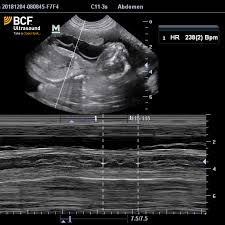

Advanced Ultrasound Techniques In Small Animal Reproduction Imaging Mantziaras 2020 Reproduction In Domestic Animals Wiley Online Library

Advanced Ultrasound Techniques In Small Animal Reproduction Imaging Mantziaras 2020 Reproduction In Domestic Animals Wiley Online Library from onlinelibrary.wiley.com